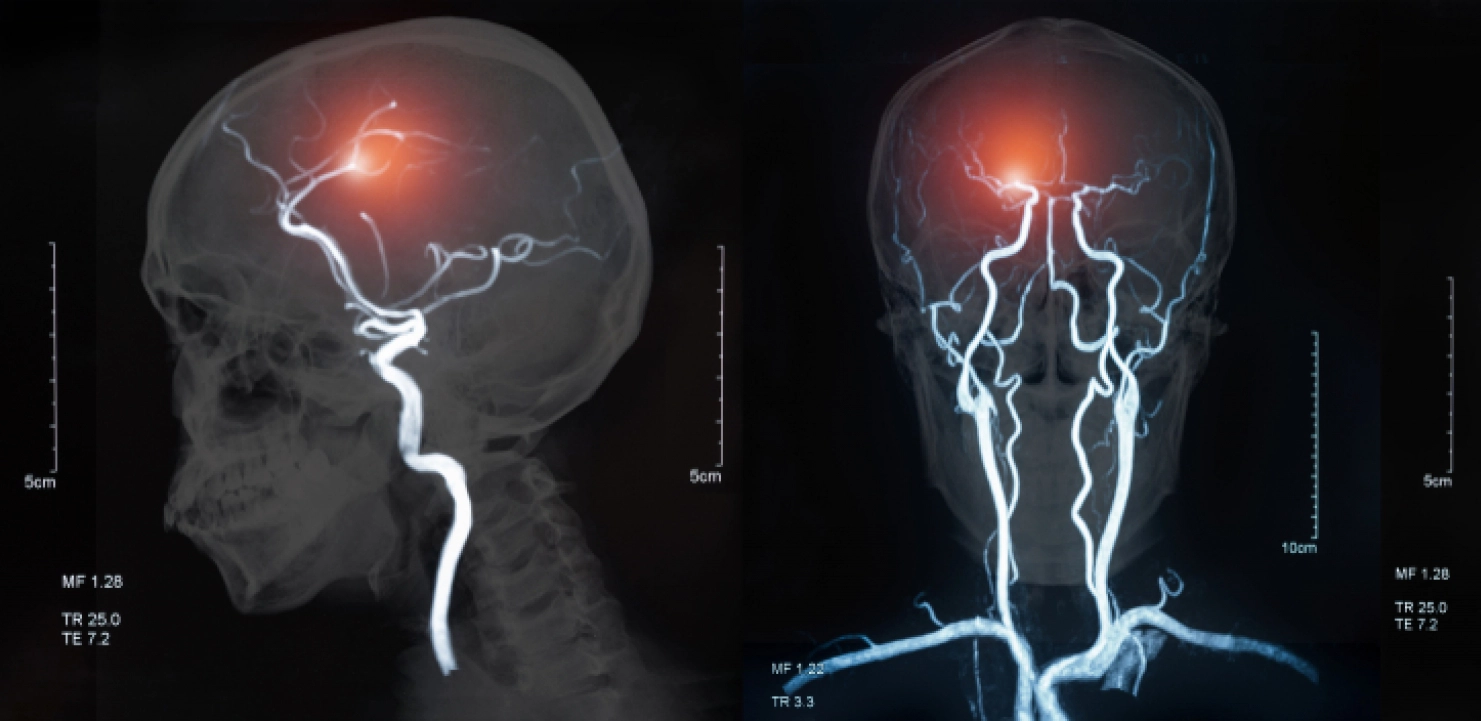

Koliko je situacija alarmantna, pokazuje i to što na svakih 20 minuta jedna osoba doživi šlog, a na svakih 60 neko umre od nastalih neuroloških posledica.

Moždani udar kosi mlade u Srbiji, a najmlađa pacijentkinja koja se jedva oporavila imala je svega 19 godina.